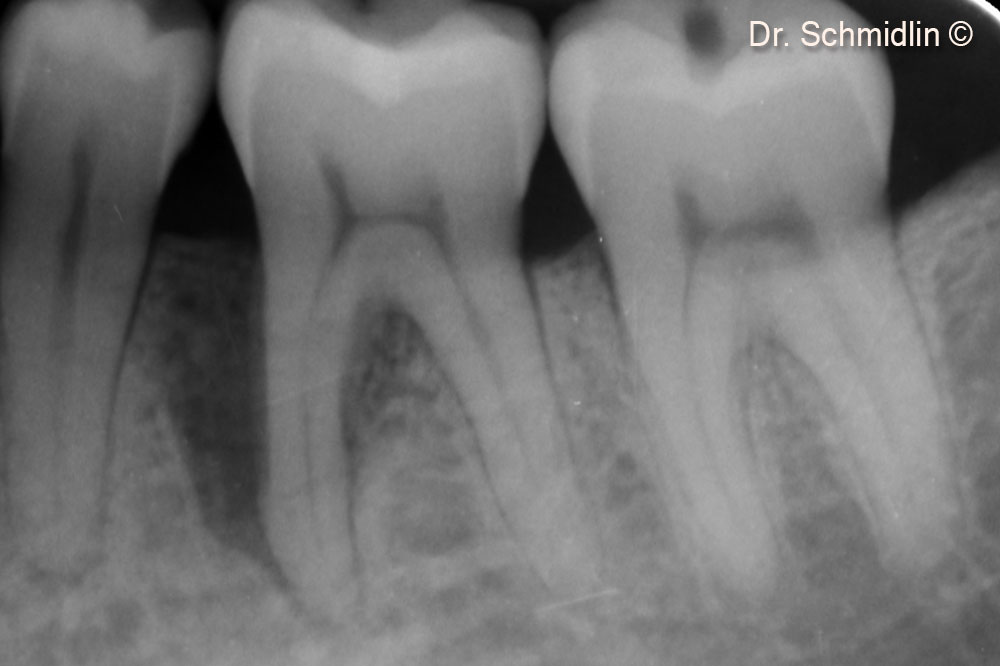

Pre-op X-Ray

Post-op X-Ray